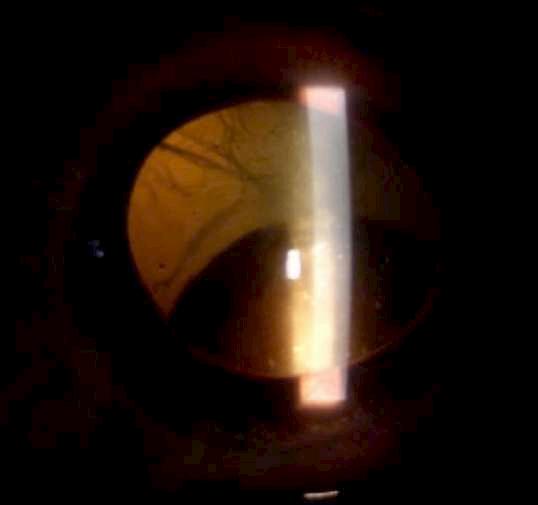

Caso aportado por Dr. Cristian Sanchez

Hombre 53 años con anteccedentes de facoemulsificación + implante de lente OD, consulta tras episodios de uveitis hipertensiva a repetición asociados a hifema del ojo derecho.

ü AV 0.7 OD

ü PIO OD: 28mmHg

ü BMC (Imagen A y B): Córna transparente, cámara anterior formada, Tyndall +, LIO in situ, transiluminación sectoriales del iris, iridotomías superior e inferior. Nevus conjuntival.

UVEÍTIS - GLAUCOMA - HIFEMA

8.C. SÍNDROME

A B

Caso

aportado por Dr. Cristian Sanchez

ü Gonioscopía (Imagen C): Ángulo abierto en en 270º, trabéculo con pigmento, SAP inferior

ü Fondo de ojo (Imagen D): Papila pálida con excavación 0.9. macula sana

ü El Sd. UGH es una complicación que puede aparecer en el post operatorio (precoz o tardío) luego de la implantación de un lente intraocular.

ü Se define clásicamente por la triada que su nombre comprende, aunque pueden aparecer formas incompletas.

ü La incidenccia se ha visto aumentada debido al incremento de la cirugía de cristalino, ya sea por catarata o con finalidad refractiva.

ü La patogenia se debe a la presión ejercida por los hápticos del lente intraocular (LIO) sobre el tejido uveal y puede presentarse en paciente con lentes en cámara anterior, sulcus o saco.

ü Sospechar en paciente pseudofáquico con episodios recurrentes de uveitis no filiada C D

8.C. SÍNDROME UVEÍTIS - GLAUCOMA - HIFEMA (UGH)

Sánchez C, Brosa H, Sanz S, Lillo J. Síndrome uveítis – glaucoma – Hipema: tres casos, tres causas. Hospital universitari de Bellvitge. Auditori Axa- Barcelona. 2016.